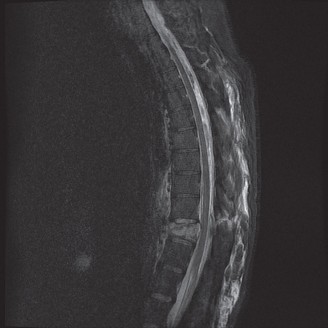

Magnetic Resonance Imaging and the Posterior Ligamentous Complex

To definitively assess the integrity of the soft tissue stabilizers and the neural elements, a Magnetic Resonance Imaging (MRI) scan without contrast was performed. Historically, textbooks propagated the "50-50-25 rule," suggesting that a burst fracture was inherently unstable if it exhibited >50% canal compromise, >50% loss of vertebral body height, or >25 degrees of kyphosis. Modern spine trauma surgery has largely debunked this rigid radiographic dogma. We now understand that these bony metrics alone do not dictate mechanical instability. The true arbiter of stability is the Posterior Ligamentous Complex (PLC).

The MRI, particularly the Short Tau Inversion Recovery (STIR) and T2-weighted sagittal sequences, provided the definitive diagnosis. The images demonstrated profound hyperintensity and discontinuity of the ligamentum flavum, the interspinous ligaments, and the supraspinous ligaments at the T12-L1 level. The facet joint capsules were also disrupted, indicated by fluid within the joints. This complete failure of the PLC means the posterior tension band is gone. Regardless of the bony parameters, this spine cannot resist physiological flexion loads. If treated non-operatively, this injury will inevitably lead to progressive kyphosis, delayed neurological deficit, and intractable pain.